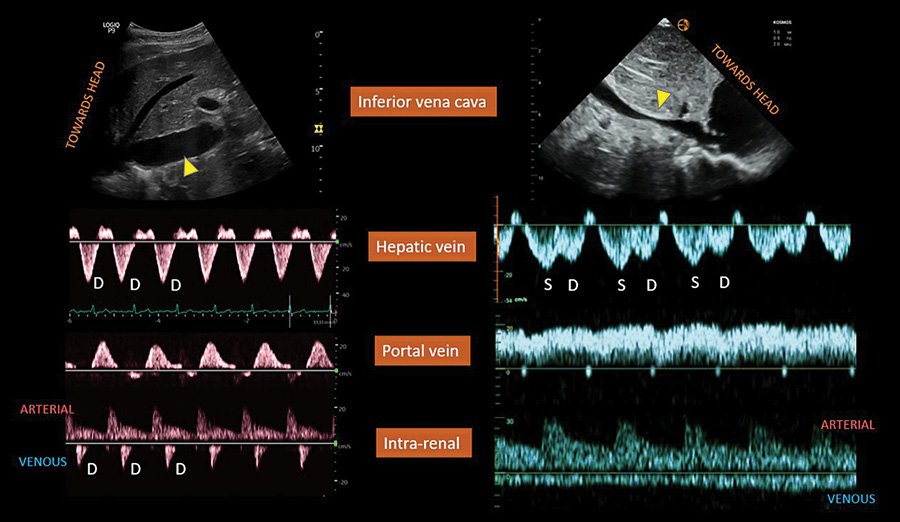

🔴 Diagnosis of Fluid Overload: From Conventional to Contemporary Concepts #openaccess #Review karger.com/crm/article/12… #FOAMed #MedEd #medstudent #paramedic #Cardiology #CardioEd #medtwitter #meded #CardioTwitter #cardiotwiteros #MedX #cardiovascular #MedTwitter #medical

🔴  Diagnosis of Fluid Overload: From Conventional to Contemporary Concepts

#openaccess  #Review

karger.com/crm/article/12…

Demonstration of hepatojugular reflux on CVP trace. #FOAMed #FOAMcc #hemodynamics Can be done using #POCUS also (see thread)